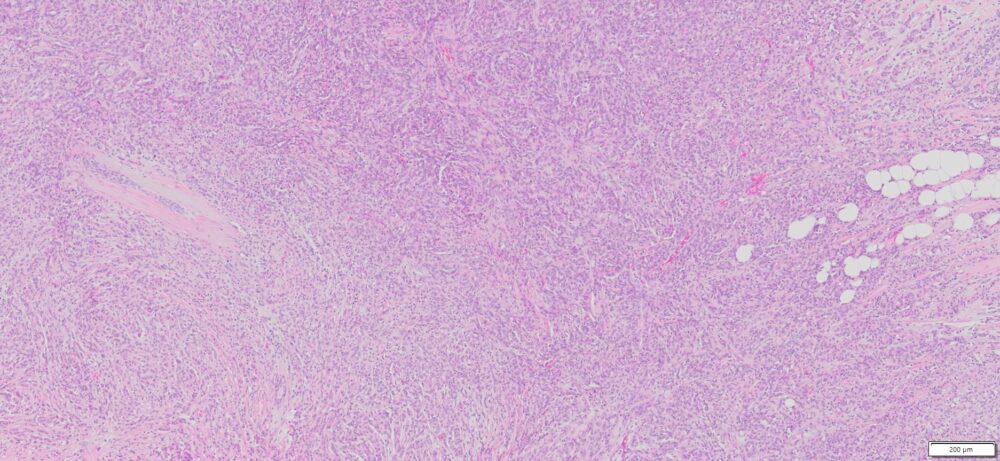

| HuPS-02030T | Breast | Invasive lobular carcinoma | No | Female/77 | 30% | II | T2N0Mx | ER(+), PR(+), Her2 (-) |